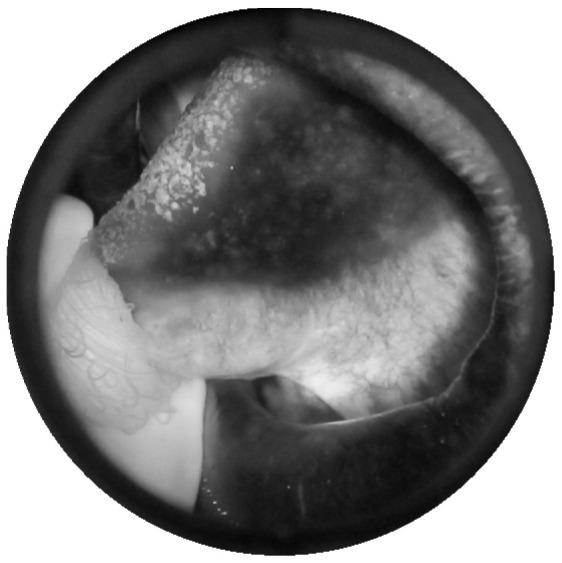

Oral mucosal lesions (OML) and oral potentially malignant disorders (OPMDs) have been identified as having the potential to transform into oral squamous cell carcinoma (OSCC). This research focuses on the human-in-the-loop-system named Healthcare Professionals in the Loop (HPIL) to support diagnosis through an advanced machine learning procedure. HPIL is a novel system approach based on the textural pattern of OML and OPMDs (anomalous regions) to differentiate them from standard regions of the oral cavity by using autofluorescence imaging. An innovative method based on pre-processing, e.g., the Deriche-Canny edge detector and circular Hough transform (CHT); a post-processing textural analysis approach using the gray-level co-occurrence matrix (GLCM); and a feature selection algorithm (linear discriminant analysis (LDA)), followed by k-nearest neighbor (KNN) to classify OPMDs and the standard region, is proposed in this paper. The accuracy, sensitivity, and specificity in differentiating between standard and anomalous regions of the oral cavity are 83%, 85%, and 84%, respectively. The performance evaluation was plotted through the receiver operating characteristics of periodontist diagnosis with the HPIL system and without the system. This method of classifying OML and OPMD areas may help the dental specialist to identify anomalous regions for performing their biopsies more efficiently to predict the histological diagnosis of epithelial dysplasia.

口腔黏膜病变(OML)和口腔潜在恶性疾病(OPMDs)已被确定为有可能转化为口腔鳞状细胞癌(OSCC)。本研究专注于一种名为医疗保健专业人员参与的人机交互系统(HPIL),通过先进的机器学习程序支持诊断。HPIL 是一种基于 OML 和 OPMDs(异常区域)纹理模式的新型系统方法,通过自发荧光成像将其与口腔标准区域区分开来。本文提出了一种基于预处理(例如 Deriche-Canny 边缘检测和圆形霍夫变换(CHT))、使用灰度共生矩阵(GLCM)进行纹理分析的后处理方法以及特征选择算法(线性判别分析(LDA))的创新方法,然后是 k-最近邻(KNN)来对 OPMD 和标准区域进行分类。在区分口腔标准和异常区域方面,准确性、灵敏度和特异性分别为 83%、85%和 84%。通过牙周病医生使用 HPIL 系统和不使用系统进行诊断的接收器工作特性来绘制性能评估。这种分类 OML 和 OPMD 区域的方法可能有助于牙科专家识别异常区域,以便更有效地进行活检,从而预测上皮发育不良的组织学诊断。